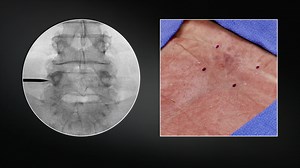

Procedure - Bilateral L3 L4-L5

Technique - Lumbar